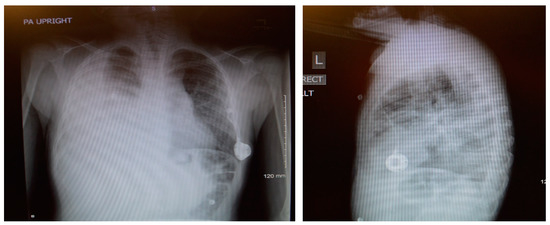

The pressure gradient necessary to open the valve is 3 cm of water, but this can be overcome by compressing the bulb which houses the one-way valve, forcing flow from chest to abdomen. This pressure gradient is noted on the packing insert for the shunt and is outlined within the instruction manual for the Denver shunt on the manufacturer, Beckton, Dickinson, and Company’s (Franklin Lakes, NJ, USA) website. The patient continued with monthly simple transfusions, and hydroxyurea was instituted. Following the PP shunt placement, he required one hospitalization for re-accumulated chylothorax and had a thoracostomy tube placed. Significant drainage was felt to be secondary to the obstruction of the PP catheter and to non-adherence regarding compressing the shunt reservoir bulb daily in order to prevent obstruction of its one-way valve. The PP catheter was cleared by pressure on the shunt bulb, which was continued at home a few times daily. Repeat imaging with Duplex ultrasound showed no change in the thrombus, consistent with fibrotic changes. The PP shunt was removed about 6 months after placement, and he has remained free of pleural effusion (Figure 7). The decision to remove the shunt was based on an asymptomatic period of about 6 months, parent comfort level, and the surgeon’s past experience with PP shunts. He has continued to be managed with hydroxyurea, with dose escalation to the maximally tolerated dose, and he has transitioned off transfusions.

Figure 7.

Most recent chest X-ray, several months after removal of shunt.